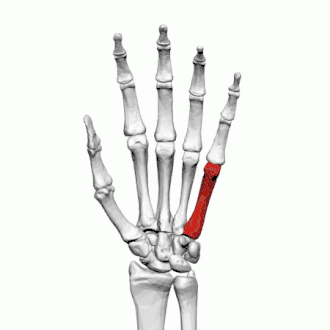

Fractures

Les fractures des os métacarpiens représentent 30 à 40 % de toutes les fractures de la main, dont 25 % surviennent dans le premier métacarpien (deuxième après les fractures du cinquième métacarpien) et 80% des fractures du premier métacarpien surviennent à sa base[2].

Les fractures courantes du premier métacarpien sont la fracture de Bennett et la fracture de Rolando.

La fracture des quatrième et cinquième métacarpien est fréquente après un coup de poing : fracture du boxeur.